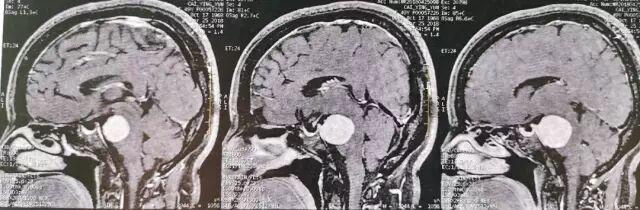

查体:神清语利,双瞳等,光反应灵敏,右侧面部浅感觉减退,行走不稳,四肢肌力基本正常。核磁共振检查见右侧岩斜区肿瘤,考虑岩斜脑膜瘤。

肿瘤强化明显,部分侵入海绵窦。

术后MRI T2加权像

术后MRI T1平扫,复查可见明胶海绵影(高信号)。

术后MRI增强核磁扫描